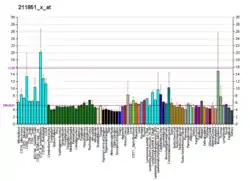

Breast cancer type 1 susceptibility protein is a protein that in humans is encoded by the BRCA1 (/ˌbrækəˈwʌn/) gene.[5] Orthologs are common in other vertebrate species, whereas invertebrate genomes may encode a more distantly related gene.[6] BRCA1 is a human tumor suppressor gene[7][8] (also known as a caretaker gene) and is responsible for repairing DNA.[9]